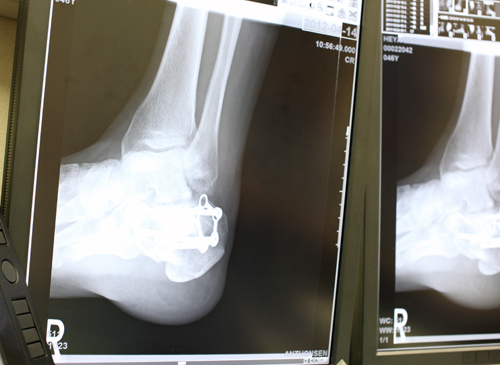

これが例の粉砕骨折、右カカト。プレートと太っといボルト4本入ってる、わかる?

経過は小山順調、うまくいけば9月にはプレート出せそう。

でもリハビリはもうちょい、ちゃんとせんといけんなぁ〜 まだまだ足首が堅すぎると指摘。